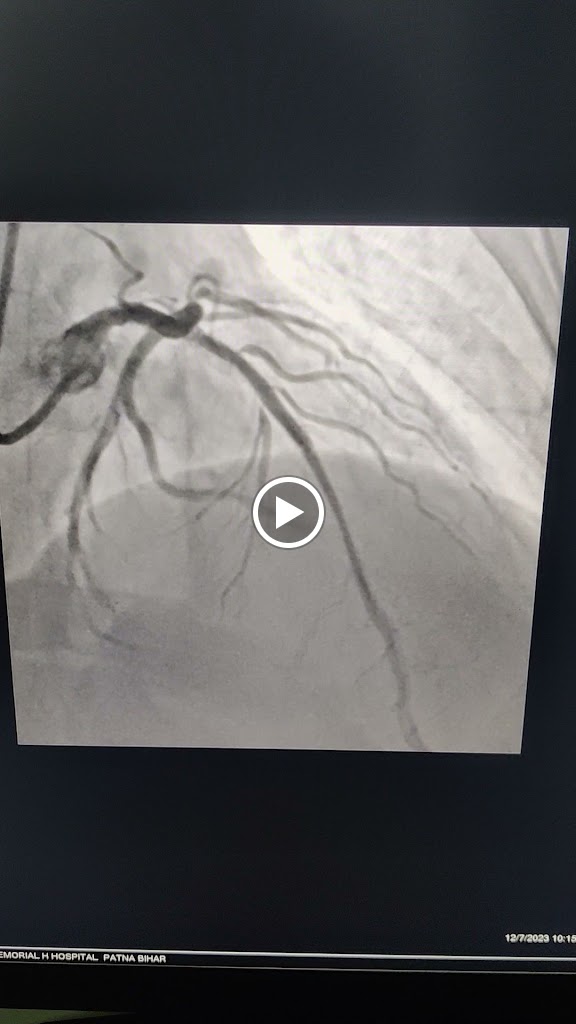

Myself Mukesh Kumar, a 41 yr old person had a severe cardiac arrest on 28th Oct'24 and attended by Dr Sumit Kumar Verma DM cardiology at Shanti Care Clinic, station road Begusarai Bihar. During angio it was observed that LAD 100% thrombotic occlusion from mid part & LCX mid part 99% thrombotic. In short, Double Vessel Coronary Artery Disease diagnosed successfully by Dr Sumit Kr Verma. I was almost dead. Not only me but also my whole family is very thankful to Dr Sumit Kumar Verma for saving my life. He is very professional, sincere, proactive and always available for his patients. He has done more than 100 cardio surgeries successfully.